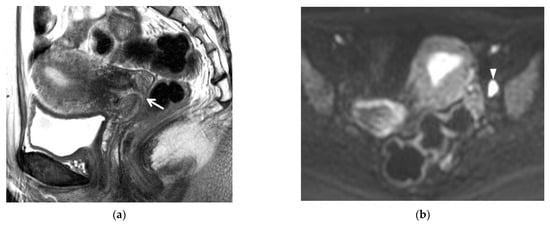

4. Post-Conization MRI

7. Early Detection of Recurrent Cancer